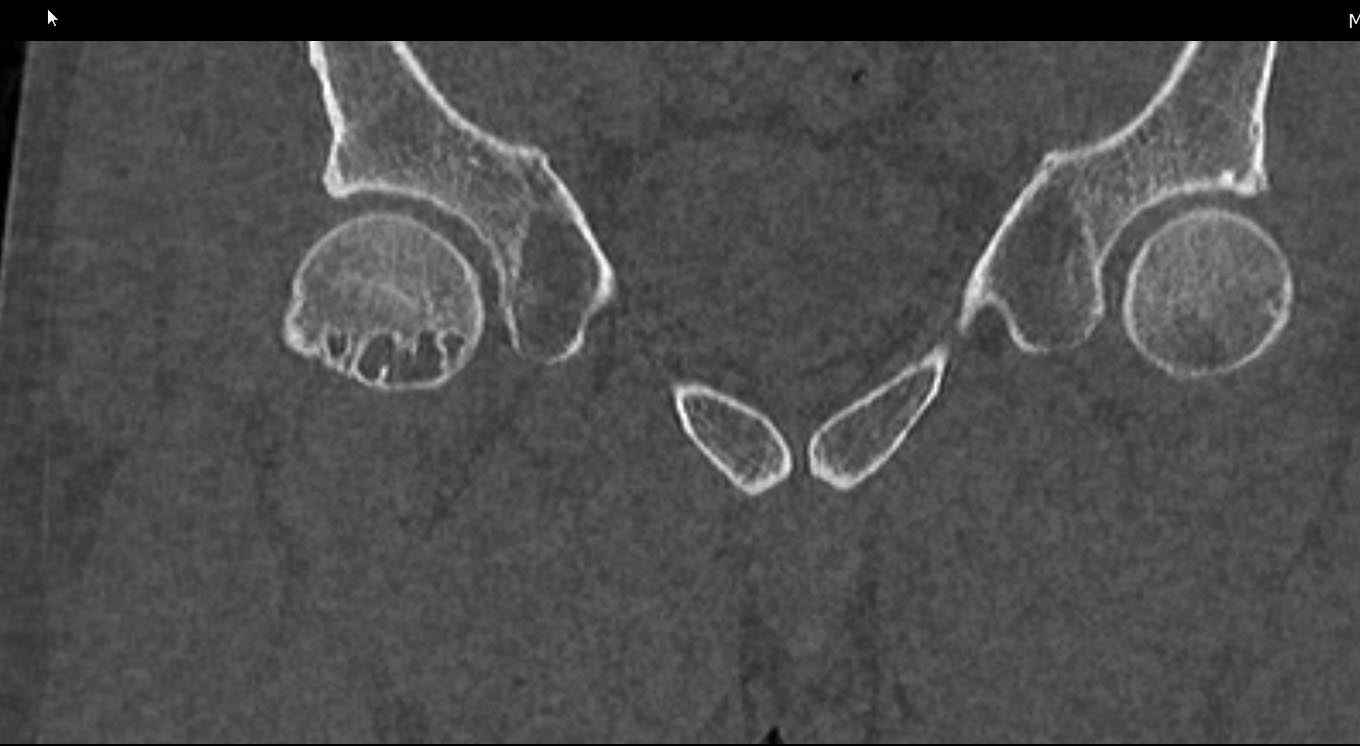

Спасибо за рентген, который подтверждает нашу догадку, но для окончательного диагноза, кроме обзорного таза, надо добавить боковой false profile снимок, где можно увидеть шейку и определить степень покрытия головки бедра во время нагрузки.

Обычно при внутрикостной кисте болевой симптом не проявляется, но капсула и лабральное кольцо из-за измененной анатомии могут быть причиной боли! Хроническая травма на шейке образует характерный бугор, меняется центр ротации, и во время нагрузки бугор выталкивает головку из вертлужной впадины. Это приводит к деламинации хряща, что не всегда определяется на рентген снимке. Поэтому следующим методом исследования становится МРТ с гадолинием, потому что другие исследования не покажут состояние лабриум и хряща!

Здесь представлены рентген, боковой, МРТ и клинические снимки деламинации хряща одного того же пациента.